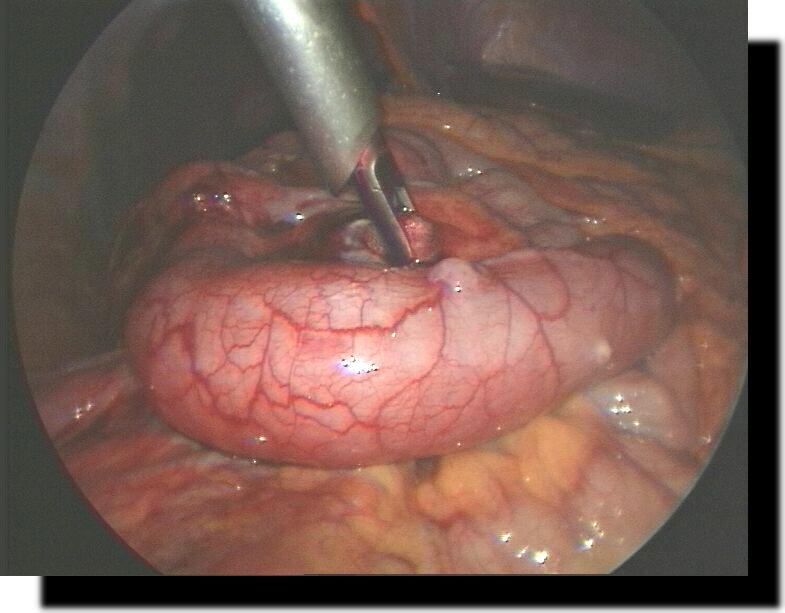

Meckel´sches Divertikel